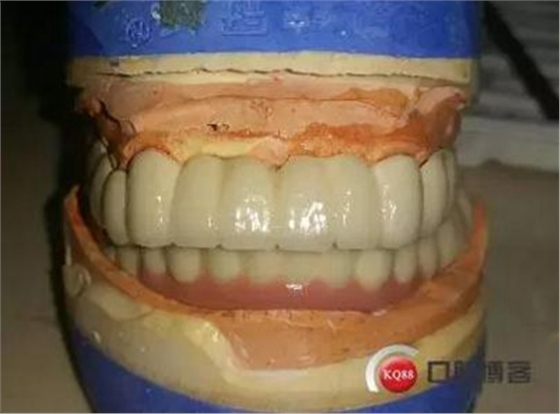

烤瓷牙回來: